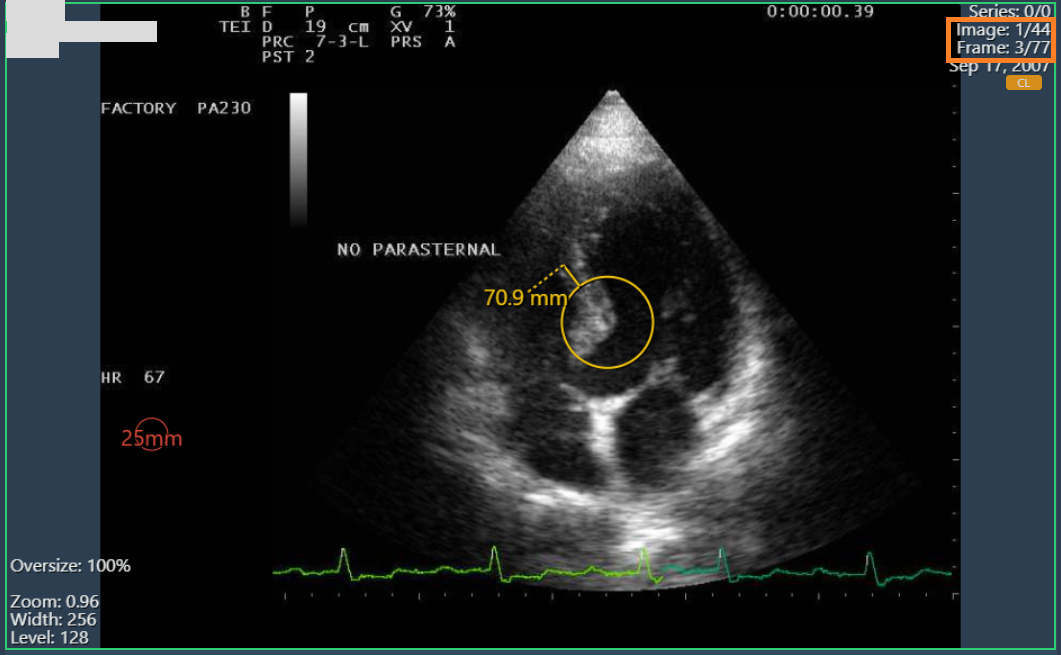

Annotations on multiframe images

Annotations on multi-frame images were not enabled independently, so they were applied to all frames of an image. Now annotations can be made and displayed on each frame as expected.

Annotations in frame 2/77

Annotations in frame 3/77